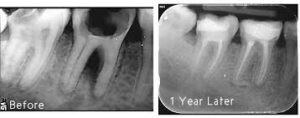

Tooth have a pulp which is the live portion of the tooth where the nerves present that extends into the root and contains nerve endings and tissues. If the nerves become infected or inflamed patient can experiences pain and swelling – then a successful root canal treatment restore the tooth rather pull it out.

Remaining the tooth in proper position prevent your other teeth from drifting out of line causing jaw-problems. By R.C.T we can avoid to replace tooth with an artificial one.